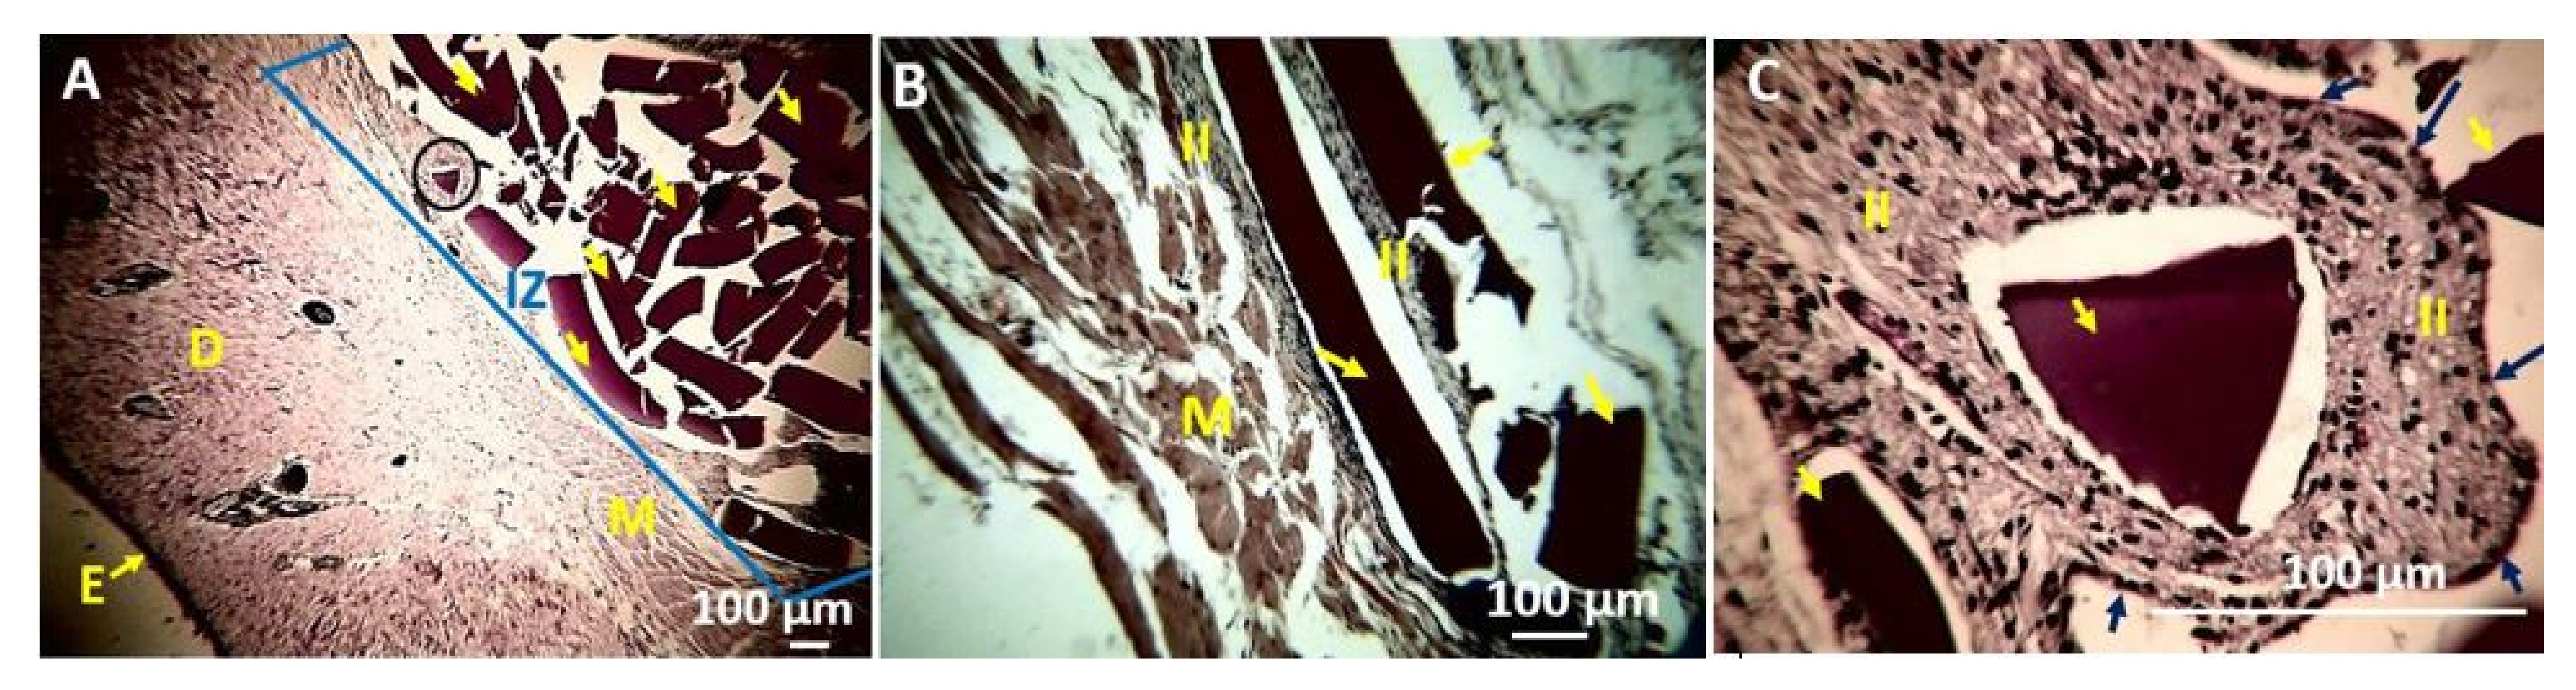

4. In Vivo Biocompatibility Tests of the CS/PVA/TTEO Films